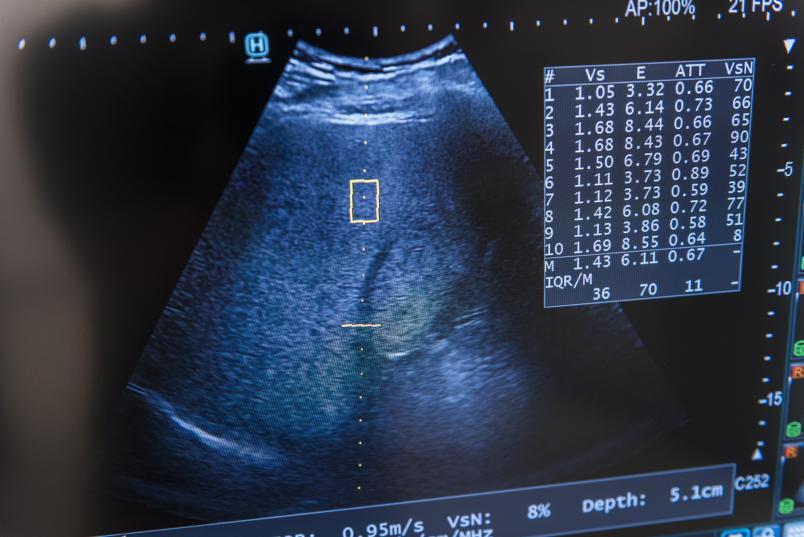

Auswertung von Bewegungs- und Schlafdaten eines speziellen Messgerätes, das im Rahmen der Studie bei Patient*innen mit Fettlebererkrankung eingesetzt wird.